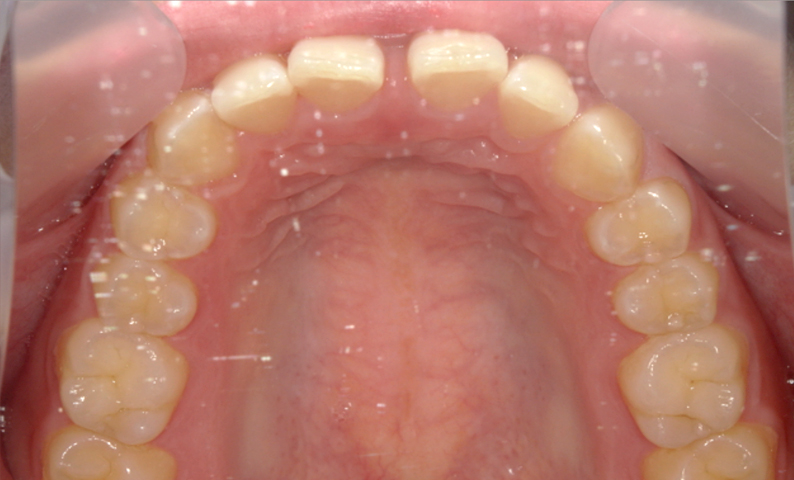

| 治療前 | 治療後 |

|---|---|

|